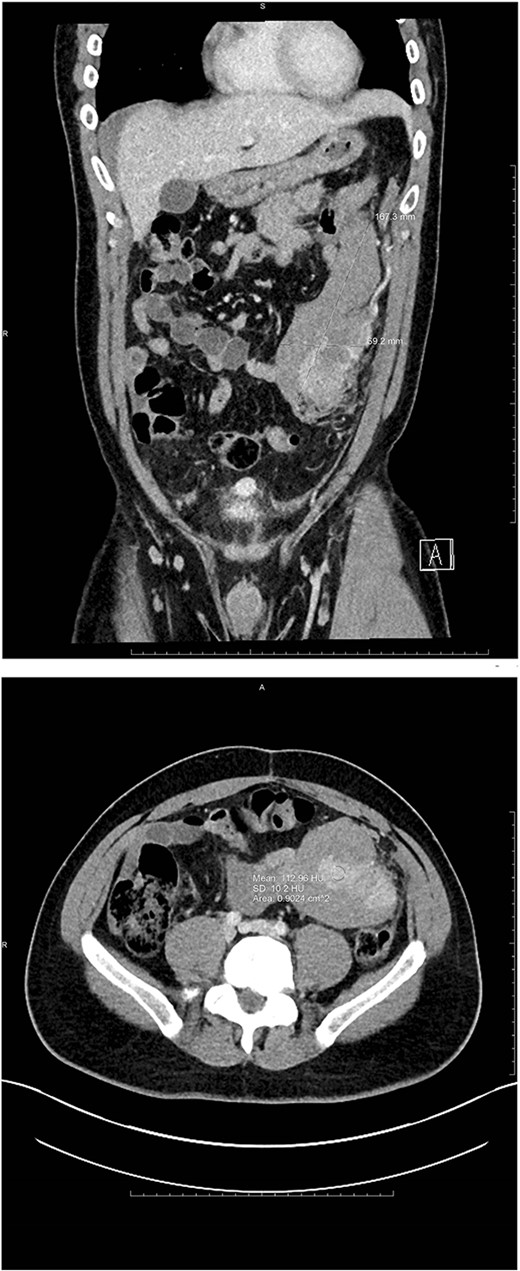

A 35-year-old male presented to the emergency department with a 1-day history of worsening left abdominal pain after reported consumption of psilocybin mushrooms. The patient denied any other inciting events or trauma. He had a history of an exploratory laparotomy and splenectomy at 12 years of age due to a traumatic sports injury and was incidentally diagnosed with splenosis in his left abdomen and pelvis at an outside hospital during a workup for abdominal pain 6 years prior to presentation. Examination revealed tenderness in the left hemiabdomen with guarding as well as hemodynamics within the normal range. Point-of-care ultrasound demonstrated fluid in Morrison’s pouch as well as a large volume of fluid in the pelvis. A computed tomography (CT) scan with IV contrast showed a large amorphous 17-cm mass-like structure in the mesentery of his left hemiabdomen consistent with a hematoma, and a multilobulated heterogeneously enhancing lesion within the lateral aspect of this hematoma. Also noted was active extravasation at the lateral aspect of the mass, arising from a vessel that appeared to be a terminal branch of the main splenic artery but that terminated into the mass within the left abdomen/pelvis (Fig. 1).

Coronal and axial views of CTA images of the abdomen and pelvis reveal a multilobulated heterogenous mass measuring 16.7 × 6.9 × 8.3 cm in the left mid-abdomen. Curvilinear foci of enhancement are visualized at its lateral aspect, originating from a prominent arterial vessel extending from the splenic artery.